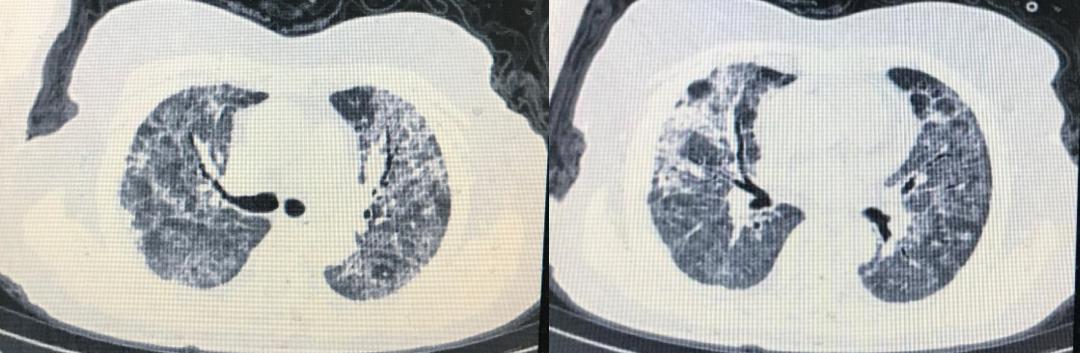

患者既往史有血糖增高,但并未作过处理,无高血压、肺病等疾病。患者入院查体的情况:T37.6℃,R32次/分,BP130/80,SPO2 76%(吸空气下),神志清,急性病容,呼吸急促,有三凹征。BMI 25。辅助检查结果为:血常规:中性粒细胞9.6×10^9/L,中性粒细胞90.4%,淋巴细胞4.3%,绝对值0.4×10^9/L,嗜酸粒细胞0.1%;白蛋白26.2g/L,BNP626pg/L,CRP37mg/L,D2聚体>8.0ug/ml,纤维蛋白原1.88g/L,肌钙蛋白29.5ng/L,LDH355U/L,血糖8.5mmol/L 。2月5日CT提示为双肺弥漫毛玻璃影,双侧少许胸腔积液(下图)。

患者的入院诊断为:病毒性肺炎,I型呼吸衰竭。入院后,患者的精神紧张,情绪低落,呼吸急促,我们立即予以鼻导管高流量吸氧,血氧饱和度在81%-92%之间波动,后改为经鼻高流量吸氧(high flows through nasal cannulae, HFNC)。

2月20日,患者的HFNC改为储氧面罩(氧流量5-7升/min),SPO2 98%,呼吸频率22次/min。患者精神、食欲明显好转,停用静脉输液。2月20日及22日复查新冠病毒核酸2次阴性。2月21日复查CT明显好转。(见下图)